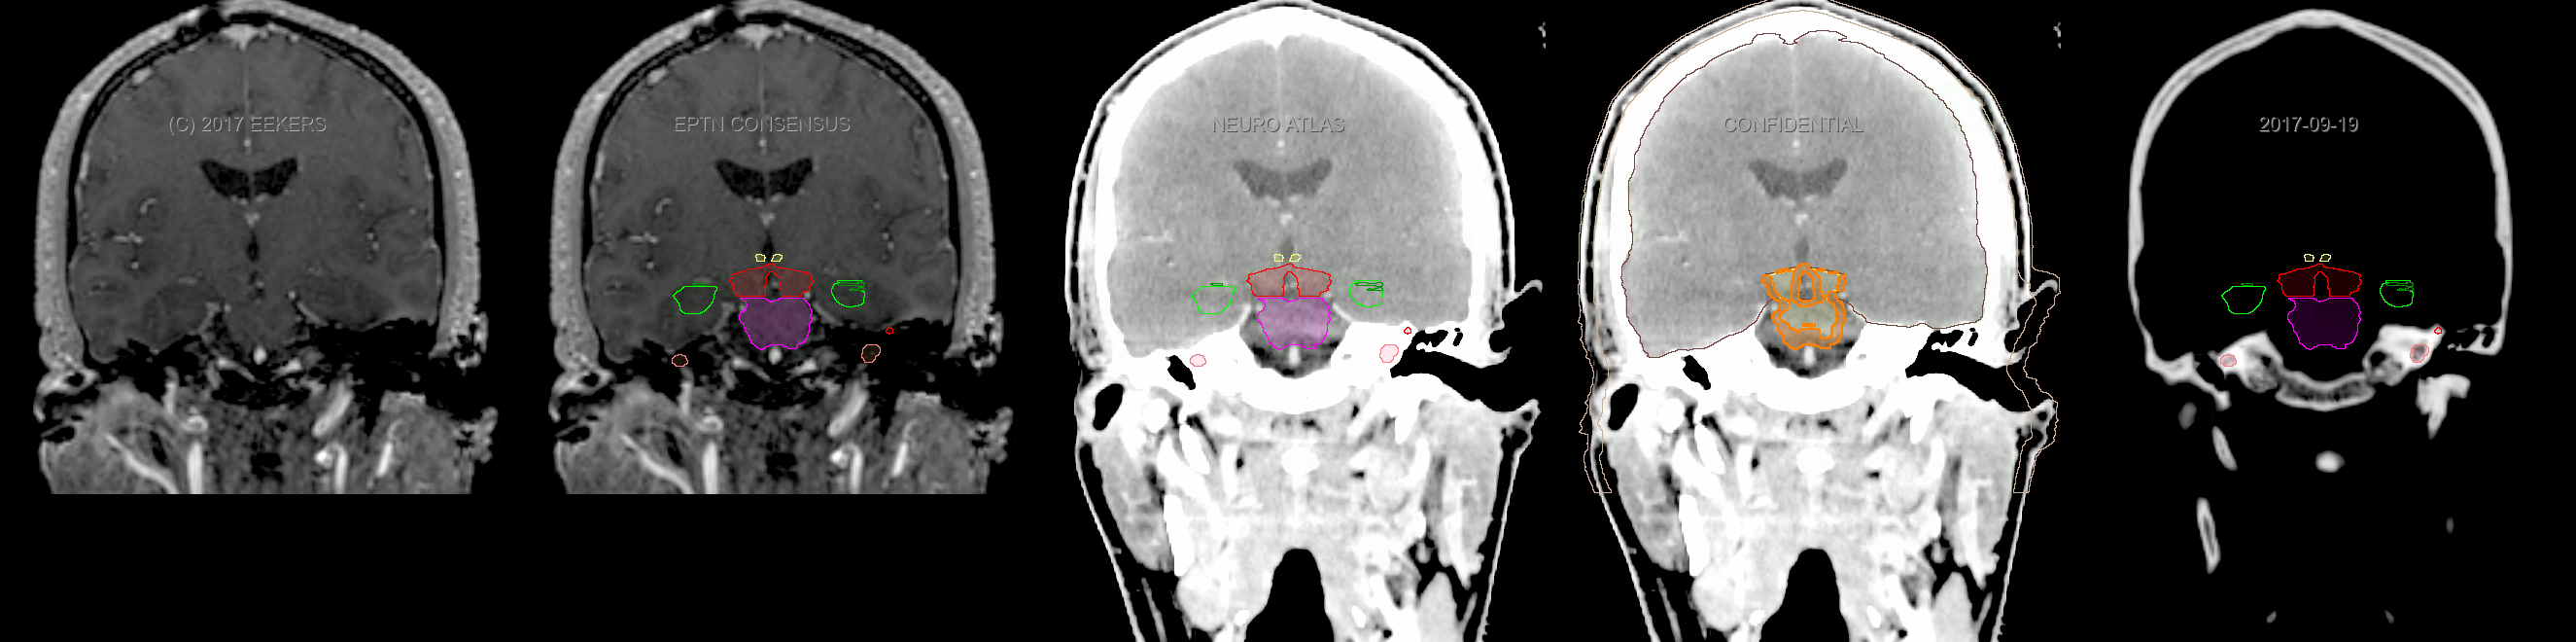

Three-dimensional delineation of the fifteen consensus OARs for neuro-oncology are shown on CT and 3 Tesla (3T) MR images (slice thickness 1 mm with intravenous contrast agent). All are presented in transversal, sagittal and coronal view.

From left to right: MR without structures, MR with structures, CT (WW/WL 120/40) with structures, CT (WW/WL 120/40) with Brain and Brainstem Surface, CT (WW/WL 1500/120)with structures